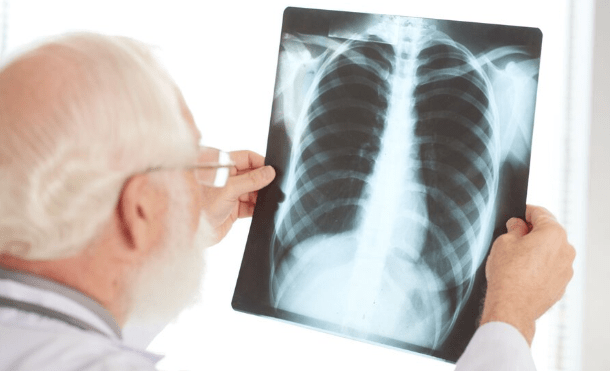

Tucumán: investigan un brote de neumonía bilateral que ya causó dos muertos

El Ministerio de Salud Pública de Tucumán advirtió que se detectó un brote de neumonía bilateral en esa provincia, donde ya se registraron seis casos, de origen y etiología desconocidos. Dos personas murieron y otras cuatro permanecen internadas. Lee esta nota en PAGINA 12